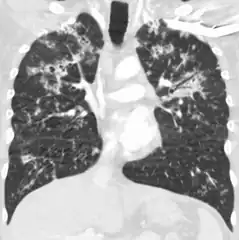

X-ray, showing bilateral interstitial infiltrates